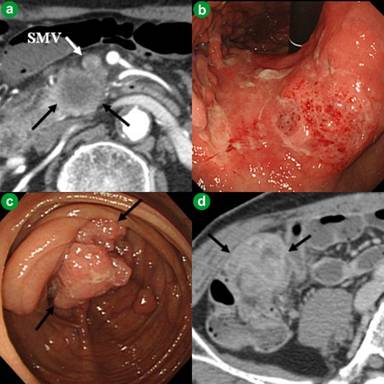

Computed tomography (CT) showed a pancreatic head mass 22 mm in diameter, accompanied by invasion of the superior mesenteric vein (Figure 1a). Upper gastrointestinal endoscopy showed a gastric tumor in the middle part of the stomach (Figure 1b), and lower gastrointestinal endoscopy and CT showed a cecal tumor (Figure 1cd). An endoscopic ultrasonography-guided fine needle aspiration (EUS-FNA) biopsy of the pancreatic head mass showed that it was an adenocarcinoma (Figure 2a), while biopsies of the gastric and cecal tumors revealed that both were well to moderately differentiated adenocarcinomas (Figure 2bc). The biopsies of the pancreatic and gastric tumors were positive for cytokeratin (CK) 7 and negative for CK20, whereas the cecal tumor was negative for CK7 and positive for CK20 (Figure 2defghi). Dual color in situ hybridization showed that the gastric tumor was positive for human epidermal growth factor receptor 2 (HER2/neu). K-ras mutations were observed in the pancreatic (glycine to valine at codon 12) and cecal (glycine to aspartic acid at codon 13) tumors, but not in the gastric tumor. Positron emission tomography revealed accumulating spots at all 3 sites, while no definite metastases were verified. Since the three tumors had different immunohistochemical and genetic characteristics, the patient was diagnosed with synchronous triple cancers of the pancreas, stomach, and cecum. The pancreatic tumor was classified as T3N0M0 and stage IIA, the gastric cancer as T2bN0M0 and stage IB, and the cecal tumor as T3N0M0 and stage IIA [10], respectively.

Figure 1. Appearance of the three cancers at diagnosis. a. Enhanced computed tomography showing a pancreatic head tumor 22 mm in diameter (black arrows) with superior mesenteric vein (SMV) invasion (white arrows). b. Upper gastrointestinal endoscopy showing a gastric tumor in the middle part of the stomach. c. Lower gastrointestinal endoscopy showing cecal cancer (black arrows). d. Computed tomography showing a large cecal tumor (black arrows). |